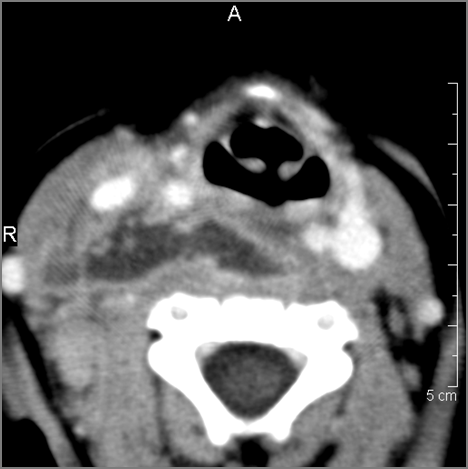

Retropharyngeal Lymph Nodes

If there is suppurative retropharyngeal adenopathy what is the maximum short axis dimension of the largest suppurative node. MEASUREMENT